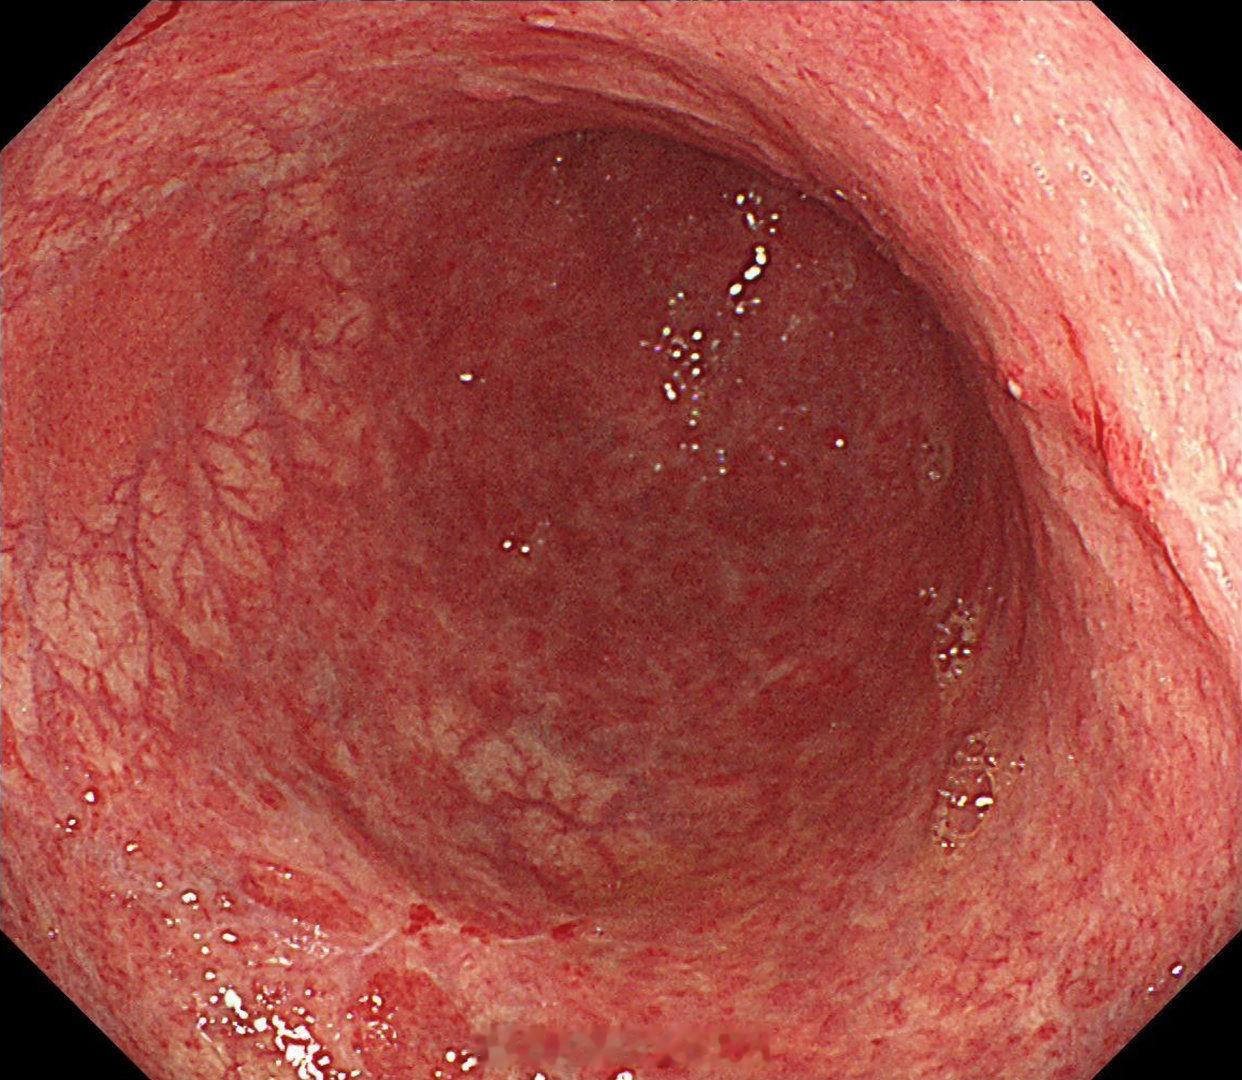

这是个常州来找我会诊的疑难杂症,当地觉得萎缩一塌糊涂,但是活检也没有提示啥病因,一开始我接诊也觉得是自身免疫性胃炎,但是抽血指标都不符合,最后在几块残余正常黏膜表现中看到了点蛛丝马迹,活检加上masson染色确诊是胶原性胃炎,以前不认识的时候这个世界都没这个病,一旦会诊断以后,满眼都是这类病[允悲][允悲][允悲]

这是个常州来找我会诊的疑难杂症,当地觉得萎缩一塌糊涂,但是活检也没有提示啥病因,一开始我接诊也觉得是自身免疫性胃炎,但是抽血指标都不符合,最后在几块残余正常黏膜表现中看到了点蛛丝马迹,活检加上masson染色确诊是胶原性胃炎,以前不认识的时候这个世界都没这个病,一旦会诊断以后,满眼都是这类病[允悲][允悲][允悲]